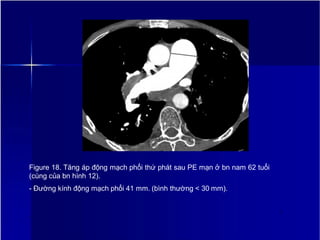

Figure 18. Tăng áp động mạch phổi thứ phát sau PE mạn ở bn nam 62 tuổi

(cùng của bn hình 12).

- Đường kính động mạch phổi 41 mm. (bình thường < 30 mm).